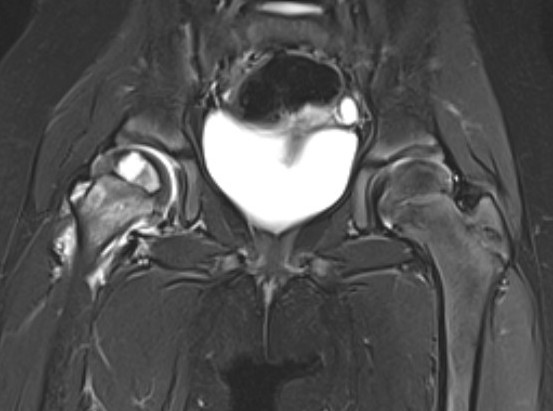

MRI

Adam et al Eur J Radiol Open 2022

- meta-analysis of MRI distinguishing between transient and septic arthitis

- bone marrow changes - 99% specific for septic arthritis

Septic arthritisSeptic arthritis

Fluid in hip joint

Hip OMHip OM

Subluxation of the hip joint with effusion and bone marrow changes

Proximal femoral osteomyelitis